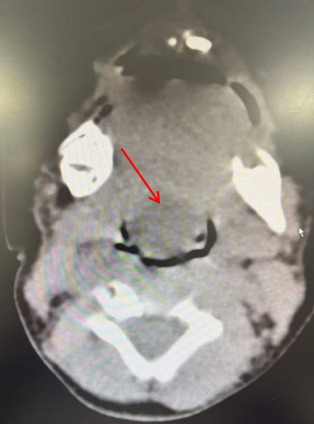

为保障手术安全,我院启动多学科协作(MDT)机制。在手术之前,由耳鼻喉头颈外科罗花南教授、任晓勇教授牵头,联合麻醉科雷晓鸣教授、超声科王华教授、影像科孙泓泓教授、新生儿科王惠萍教授开展了术前MDT讨论。麻醉科雷晓鸣教授根据患儿气道特点制定预案,准备低龄患儿的麻醉插管专用设备及耗材,并演练应急方案;影像科孙泓泓教授仔细阅读了患儿的影像学资料,认为会厌囊肿的可能性更大,甲状舌管囊肿的可能性较小,从而为制定手术方案提供了重要参考;超声科王华教授提前研究患儿的病例资料,明确超声定位方式,确保能清晰显示囊肿与神经、血管的关系,为术前囊肿减压、提高手术安全性,提供精准指引;新生儿科王惠萍教授对患儿术前插管、术后处理等围手术期管理方面提出了重要指导,并建议患儿手术结束后转至新生儿科病房留观,从而保障手术安全。